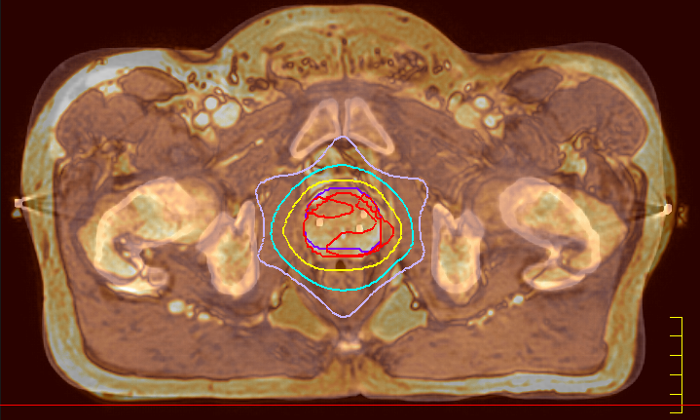

Ingenia MR-RT is a dedicated MR simulation platform that provides high quality, high contrast MR images acquired with the patient in treatment position. Designed for the needs of radiation oncology, this comprehensive solution provides the tools and software needed for versatile and efficient imaging for radiotherapy planning.

Our innovative MRCAT (MR for Calculating ATtenuation) clinical applications lets you plan radiation therapy using MRI as primary imaging modality. Within just one, fast MR exam, MRCAT provides both excellent soft-tissue contrast for target and OAR delineation and CT-like density information for dose calculations.

This not only extends the benefits of MRI’s excellent soft-tissue contrast to radiotherapy planning, but it also eliminates arduous, error-prone CT-MRI registration from the process, reducing uncertainties and complexity.